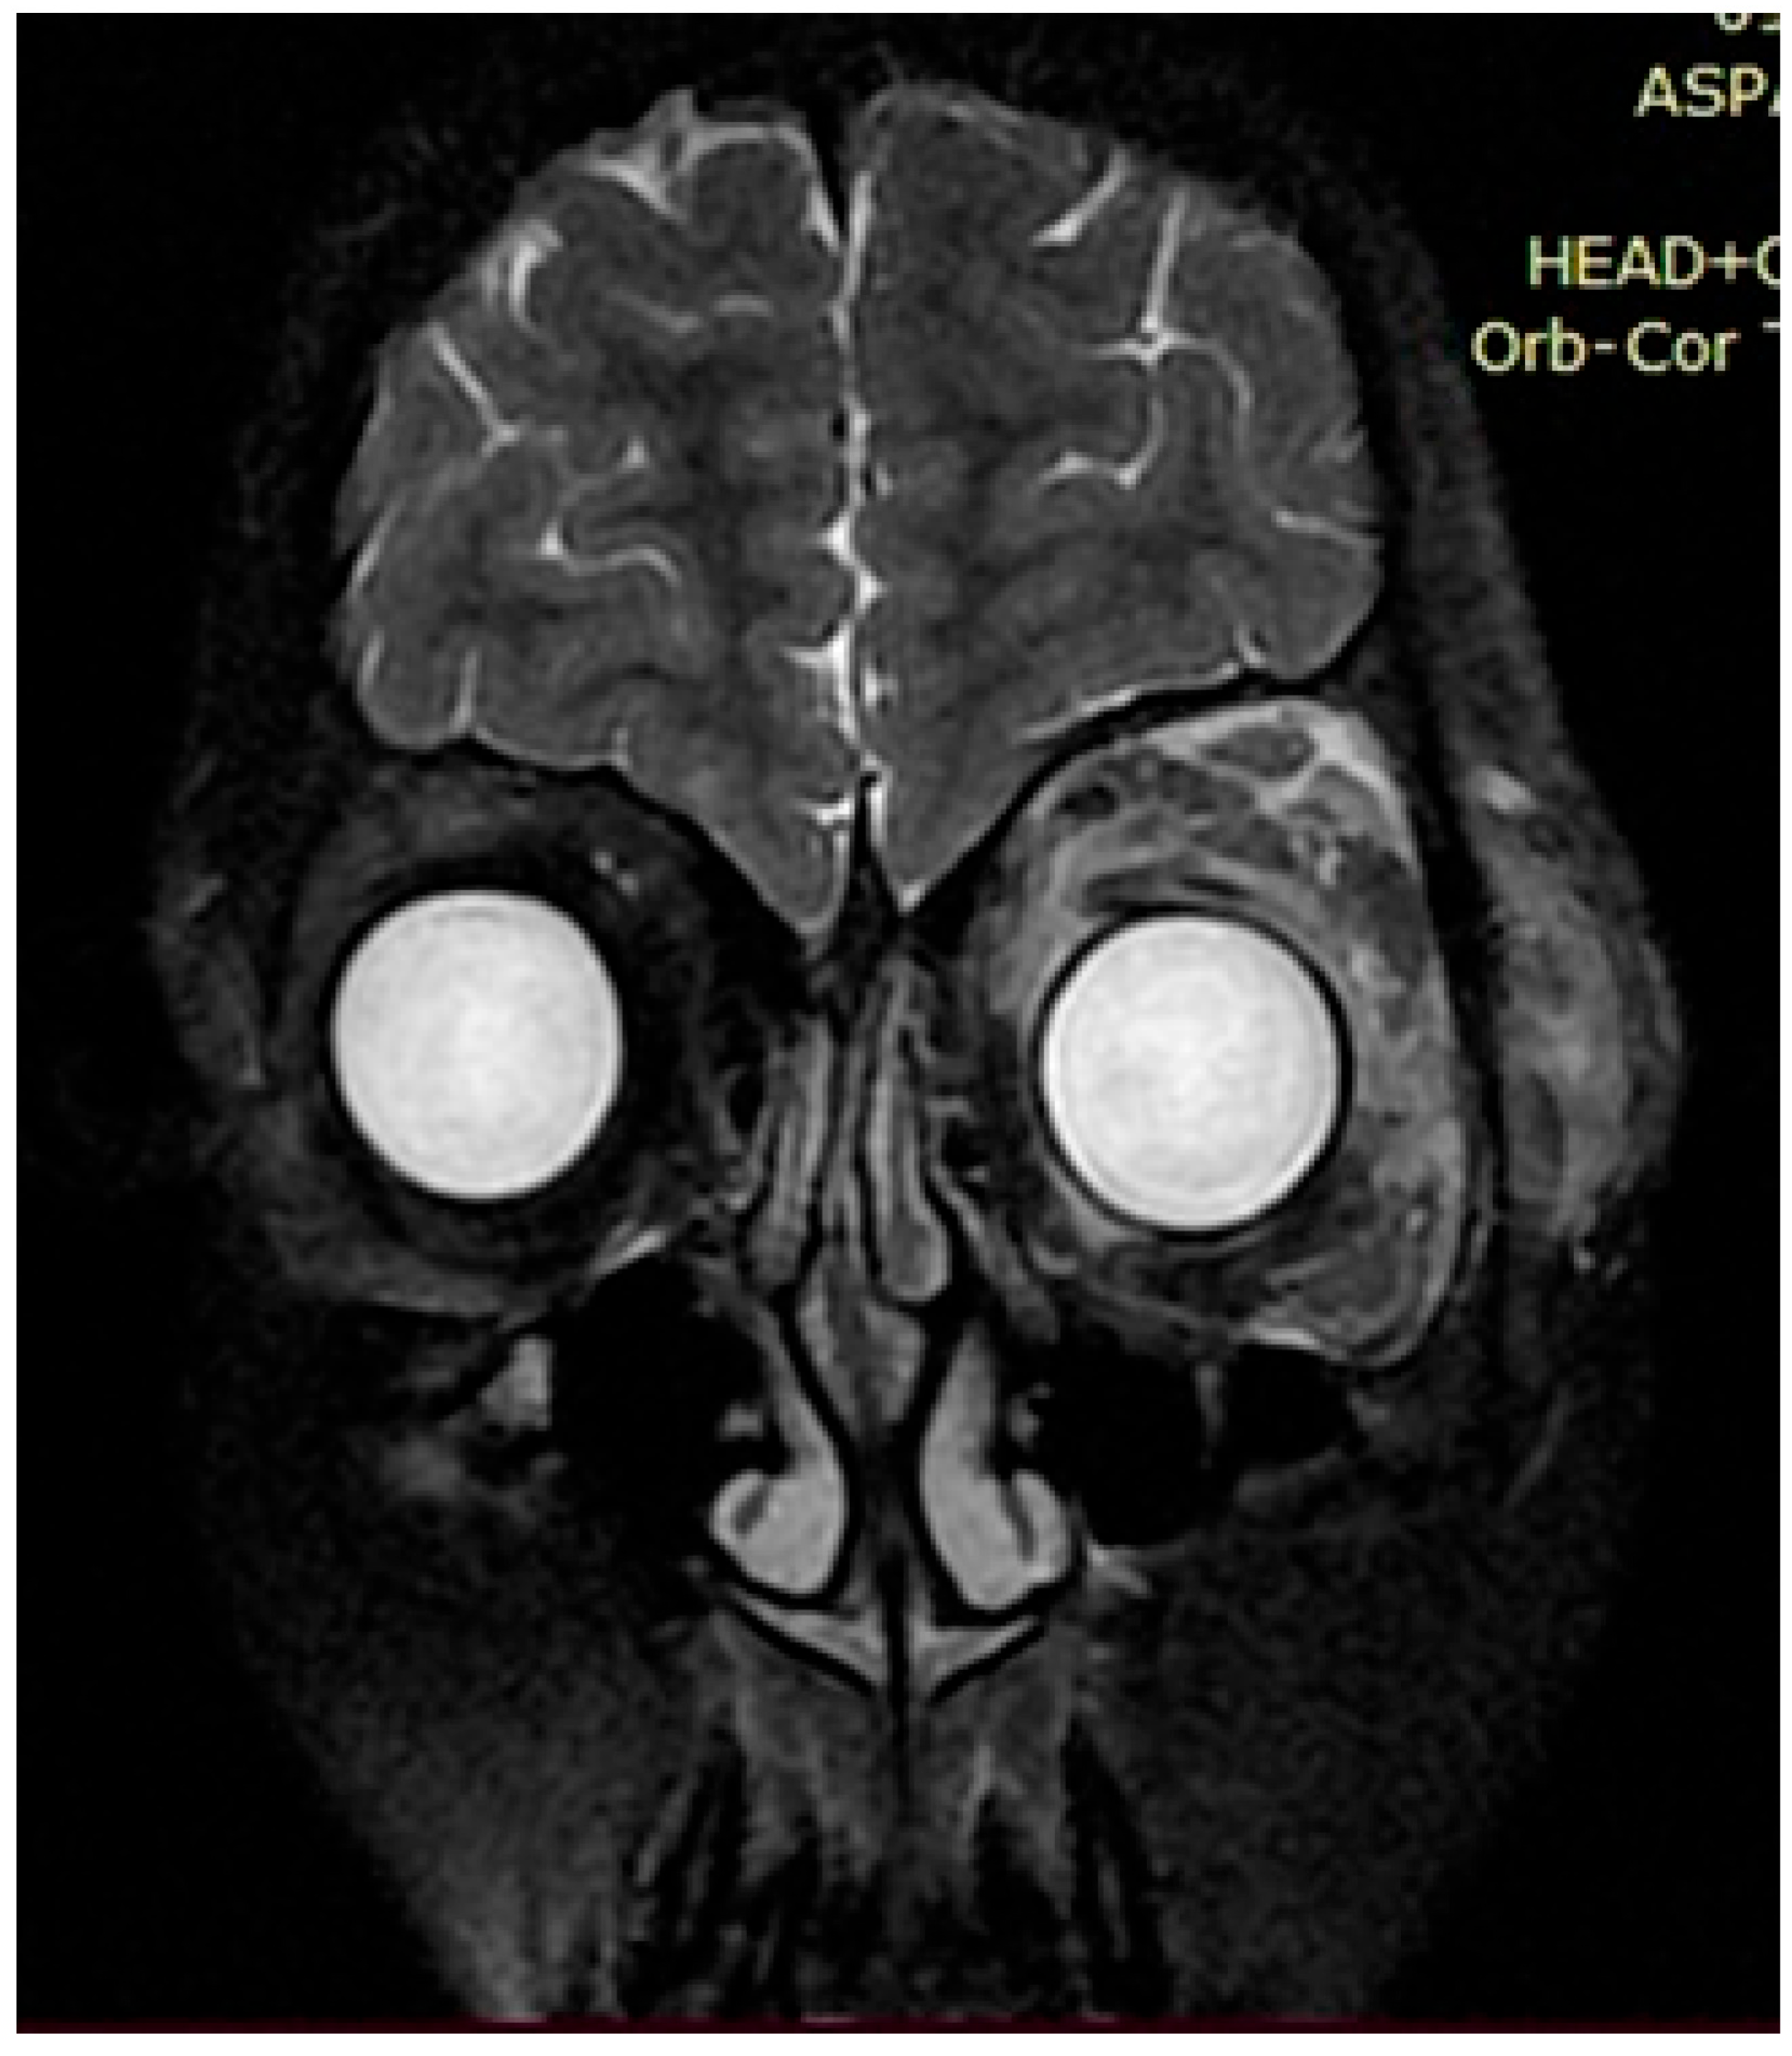

Upon further growth of neural tissues, patients presented with plexiform neurofibromas, located around the eye tract, neck, spinal cord, and groin (examples presented in Figure 3, Figure 4 and Figure 5). A total of 14 patients presented with optic nerve and optic tract glioma as well as retinopathies, retinal angiopathies, declined vision, astigmatism, and other eye pathologies. Many patients complained that eye plexiform neurofibroma occluded their vision, causing gradual vision loss due to lack of accommodation and increased tissue growth.

Figure 4. Case 2, clinical diagnosis of a 12-year-old boy: neurofibromatosis type 1, plexiform neurofibroma of the left periorbital region, mild truncal ataxia, and mild dysmetria. With single nucleotide replacement variant NF1 Chr17 NM_000267.4:c.5792G>A.

Figure 5. Case 3, clinical diagnosis of a 6-year-old girl 6: neurofibromatosis type 1, plexiform neurofibroma at the level of the right greater wing of the sphenoid bone with dysplasia, narrowing of the right retrobulbar space, with compression of the right optic nerve (over a length of 1.0 cm) and the superior and lateral rectus muscles of the right eye. NF1 gene genotyping: Chr17: 29576060 NM_001042492.2:c.4033A>T p.Lys1345Ter.